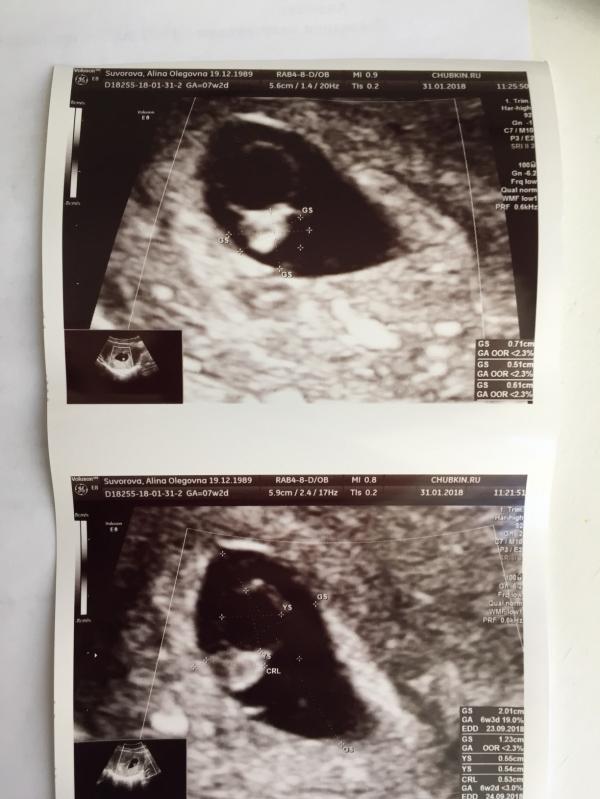

Овуляция точно 25.12. Без вариантов. 9.01 суперяркие //. Сегодня должно быть 7+2, но на УЗИ (Узист шикарный) ктр 5 мм, сб нет. Отправил гулять ещё на недельку в надежде на чудо, но шансов не много, я и сама это чувствую. Было у кого-то при подтверждённый овуляции(!) такое отставание? Мне слабо верится, что подобное возможно. Тест бы и не показал таких полосок в 3 недели, а ведь если бы сейчас было 6 недель, то 9го было 3

Тут эмбрион есть, малюсенький, но ничего не билось. Я очень хорошо помню сердечко сына на таком сроке. Ну и странные если честно соотношение пя и жм. В общем мне тяжело верить в лучшее

Подняла все УЗИ .Было так ! Овуляция 23.09 точно ! Тогда же и ПА . 7 .10.тест положительный . 12.10 узи ни ПЯ ни чего , 22.10 плодное яйцо в полости матки соответствует 7 неделям бер. СБ нет . ХГЧ растёт .10.11 по мес. ( которые были 2.09) 9 нед. 6 дней. По УЗИ прогрессирующая бер. 8нед. 6 дней. На первом УЗИ пророчили внематочную ,сейчас уже 7 месяцев моему карапузу. Так что верим что всё будет ХОРОШО !